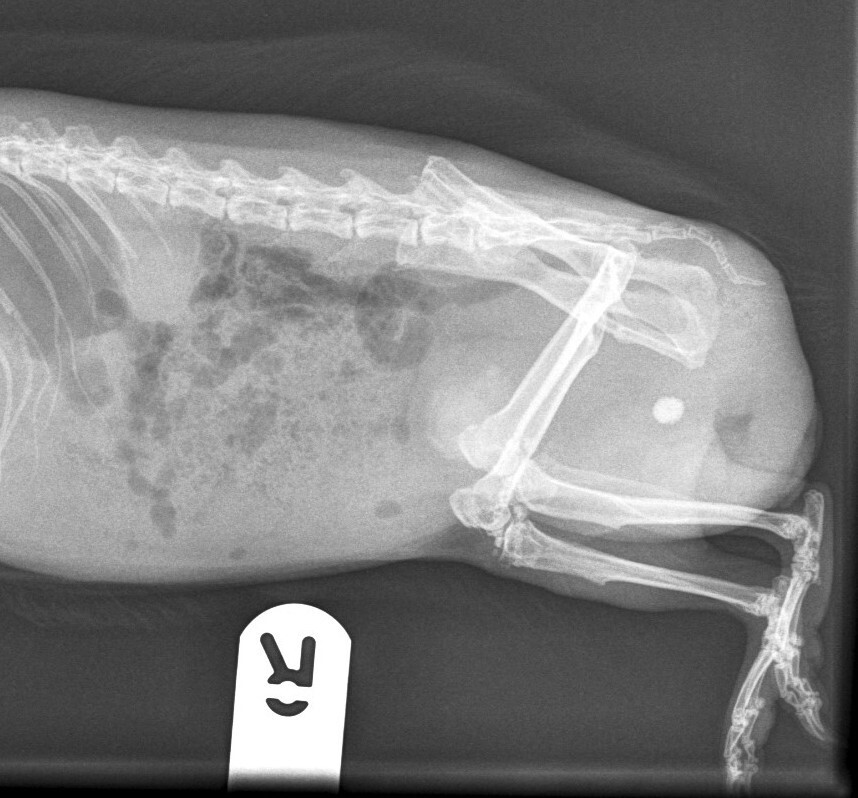

Common symptoms of urolithiasis in guinea pigs include stranguria, haematuria and signs of discomfort or pain when urinating, such as vocalisation. Diagnosis of urolithiasis in guinea pigs is similar to diagnosis in rabbits, using physical examination, urinalysis and imaging techniques, such as radiographs or ultrasound. Radiographs will often reveal the presence of stones (Figure 4), though small stones may be missed if they are not radiopaque. Ultrasound can be particularly useful for detecting smaller stones or those located in the kidneys or ureters.